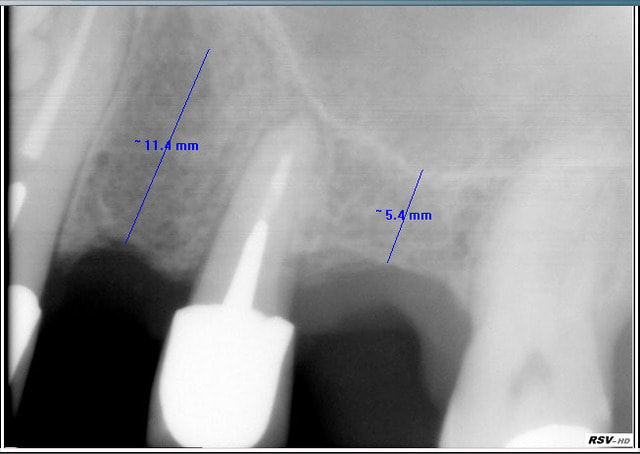

Comment traiteriez vous ce cas au maxillaire supérieur, secteur postérieur :

et surtout combien d'implants et en quelle position !

Il y a que des rvg, je sais, je sais il faut d'abord fr 1 examen endobuccal , type de gencive, HBD, ligne du sourire , occlusion etc...

Je lui ferai un cone beam s'il donne le feu vert sur le devis.

Pas compliqué : besoin de gagner plus de 2 mm sous le sinus? => sinus lift par voie latérale,

moins de 2mm ? => summers

Autre chose : tu ne peux pas mesurer sur une rétro-alvéolaire, il te faut impérativement un scan ou cone beam.

Même si l'imprécision n'est que d'1 mm, cela peut changer le plan de traitement.